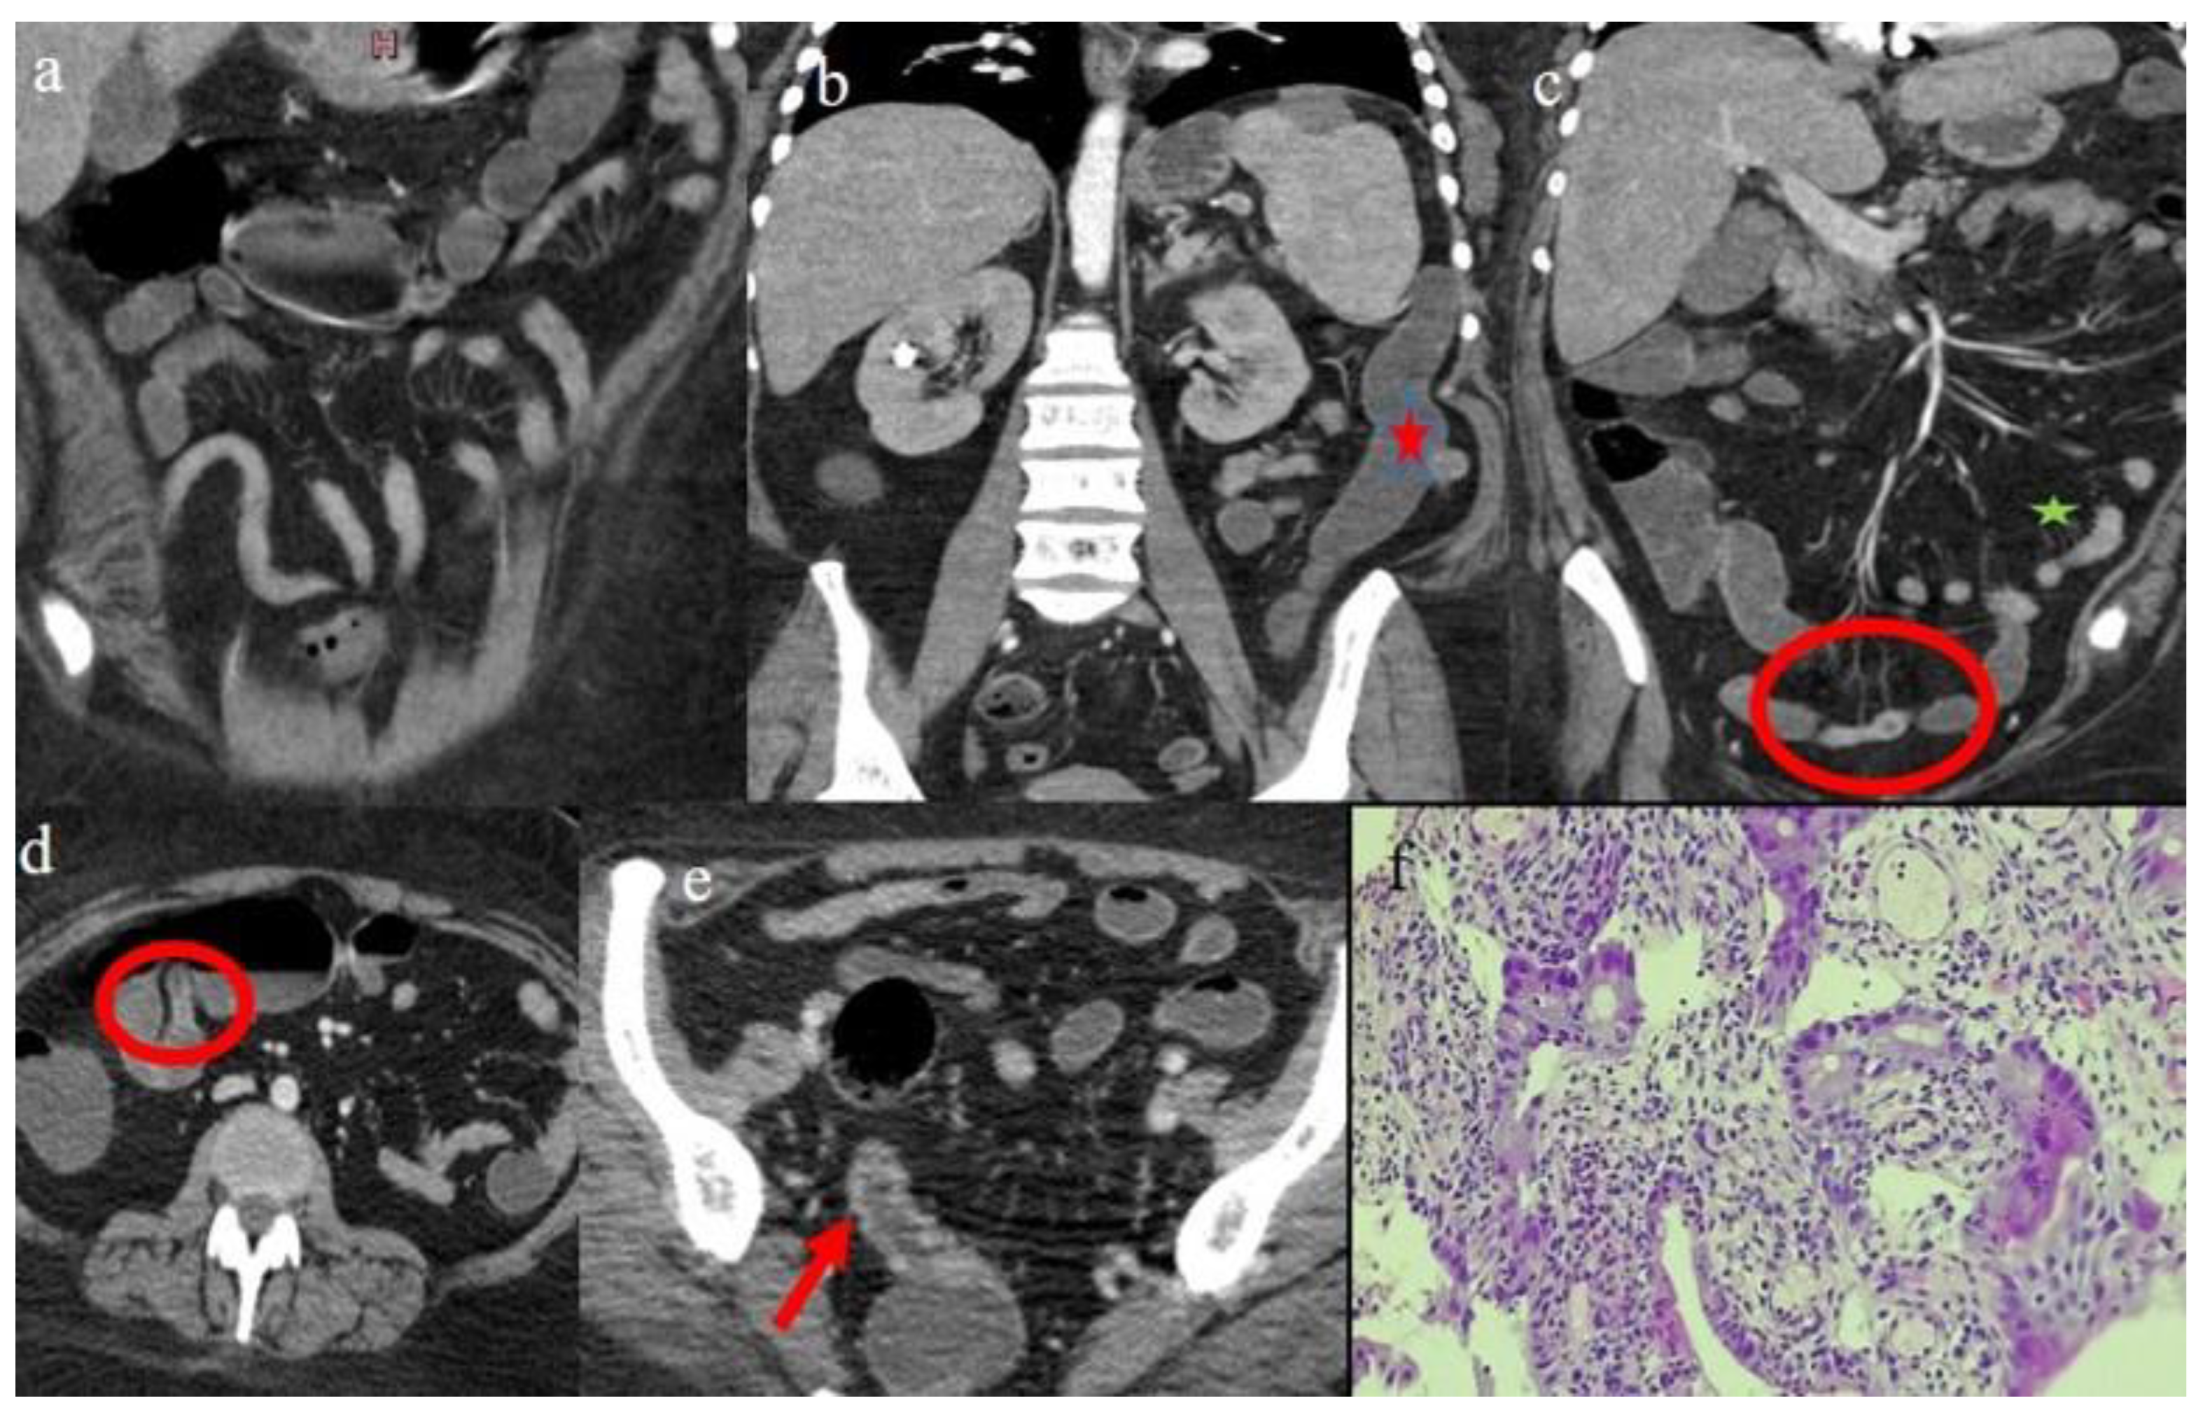

| 1 | P | P | Multisegmental and plurifocal parietal thickness with homogeneous mucosal enhancement on distal ileus | Multisegmental thickness with homogeneous mucosal enhancement | Mild diffuse comb sign and poor reactive mesenteric lymph node | Splenic infarct |